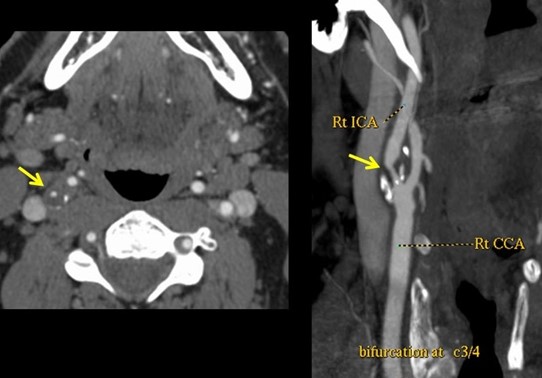

Maladie des vaisseaux du cou (artères carotidiennes)

La cause la plus fréquente d’une sténose (rétrécissement) carotidienne est l’athérosclérose (développement d’une plaque d’athérome qui se forme par dépôts de lipides).

Une sténose carotidienne est considérée comme une des causes d’AVC (Accident Vasculaire Cérébral) ou AIT (Accident Ischémique Transitoire).

Ceci se manifeste par un déficit neurologique brutal : une paraplégie d’une jambe ou d’un bras, des difficultés à trouver la parole ou la perte de vue d’un œil.

Angio-CT ou Angio-IRM des vaisseaux du cou

Lorsqu’un echodoppler conclut à une suspicion de sténose supérieure ou égale à 70%, il est nécessaire de procéder à un examen plus détaillé en radiologie